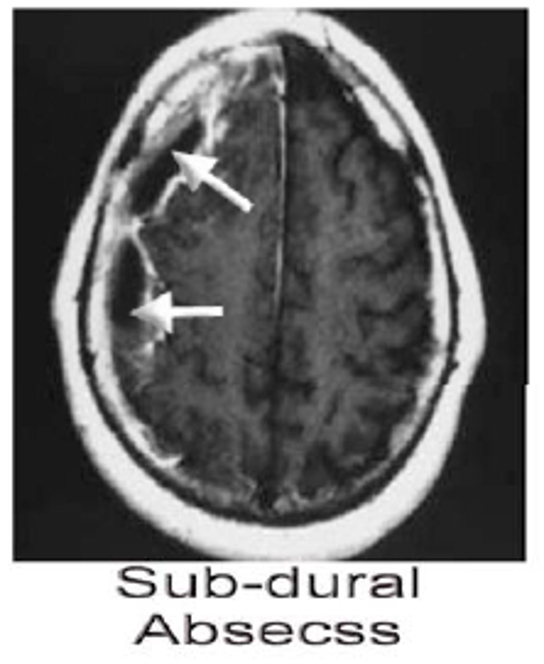

Subdural Abscess

- Definition: Collection of pus between the dura and the arachnoid.

- CT scan, MRI